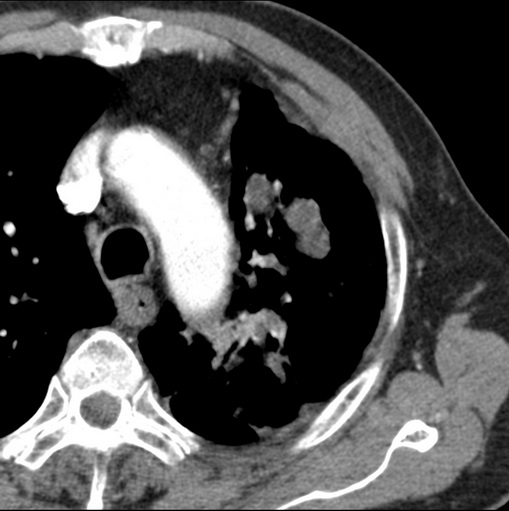

男性患者 81岁 咳嗽 咳痰 咯血

强化较典型,左上肺癌并纵膈淋巴结转移;左上肺结核并空洞形成;胸膜增厚.

肿块贴近左肺门,包绕左上肺动脉,形态不规则。肿块增强扫描中度强化。纵膈内主动脉弓左旁间隙、气管隆突前、下间隙见多枚淋巴结影。综上考虑左侧中央型肺癌可能性大。图片没有完整上传,尤其是左肺上叶支气管分支层面没有上传,因此不好判断是叶支气管中断还是段支气管中断。另外,下图红色部分所示是“黏液支气管征”吗?